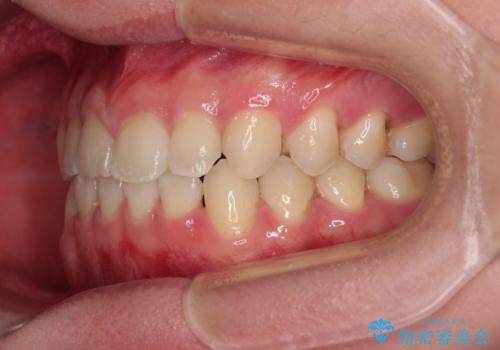

隙間とデコボコを治したい ワイヤー装置による矯正治療

- 前歯のデコボコと隙間を気にして来院された患者様です。

治療手段としてはワイヤー装置でもインビザラインでも可能でしたが、インビザラインの自己管理は自信がないとのことで、ワイヤー矯正により隙間を閉じていくこととしました。

隙間の原因は舌の突出癖であったので、舌癖改善のためのトレーニングを指導しながら治療を進めて行くこととしました。

舌の突出癖がなかなか改善されず、治療開始時よりも隙間が大きく開いてしまう時期がありましたが、最終的にしっかりと閉じて終了することができました。